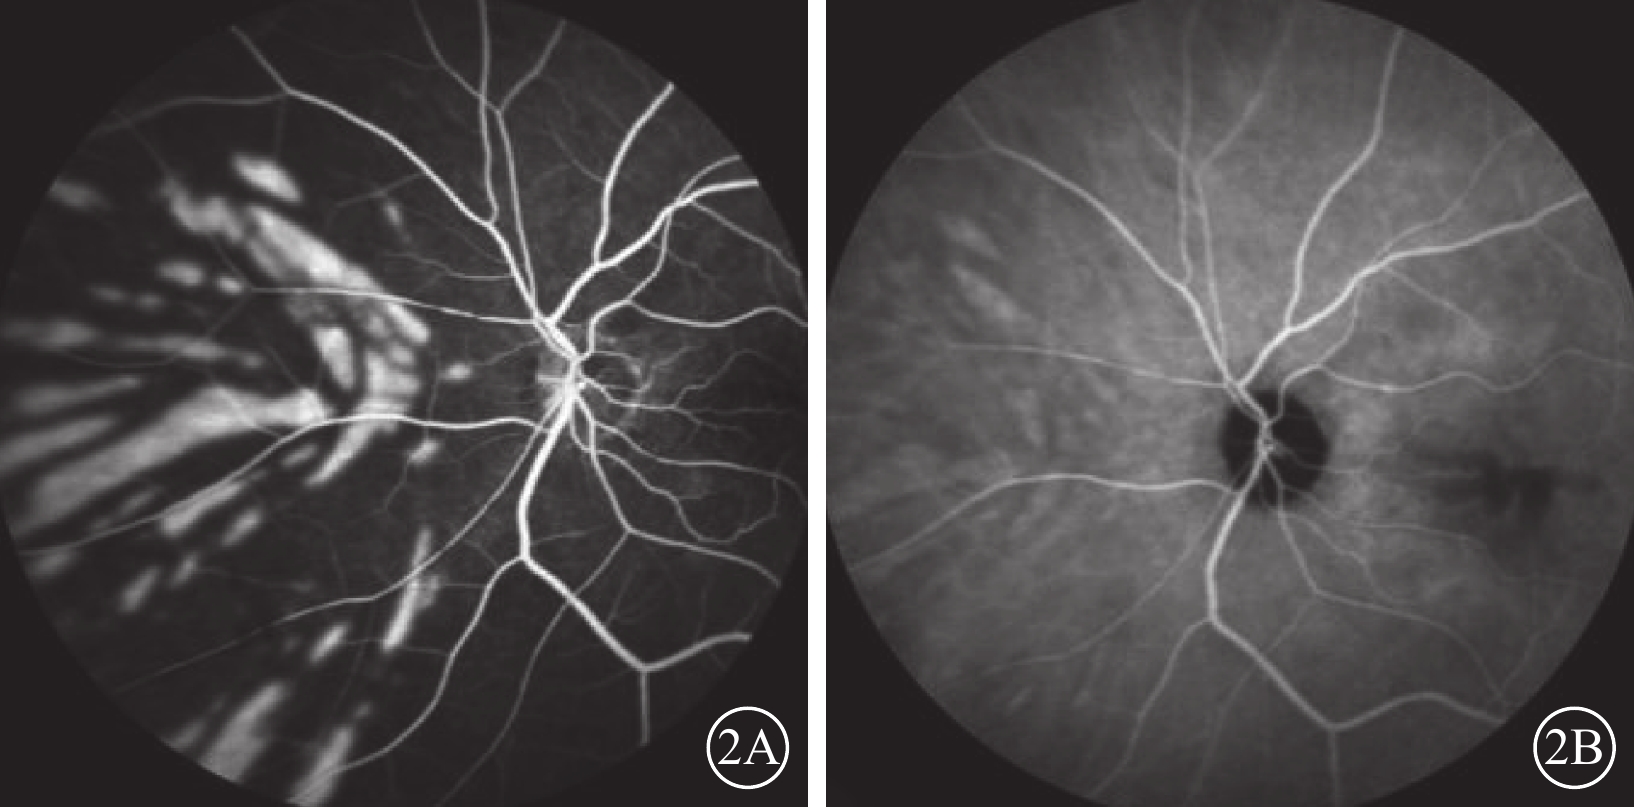

患者女,77歲。因左眼視力下降8個月加重1個月于2017年10月26日至北京大學第三醫院眼科中心就診。既往曾有晨起時一過性左眼黑矇史;否認高血壓、糖尿病等全身病史。甘油三酯輕度升高,出凝血時間正常。眼部檢查:左眼視力0.1,矯正不能提高;右眼視力0.2,矯正視力0.3。左眼眼壓(IOP)20 mmHg(1 mmHg=0.133 kPa)。晶狀體核性混濁;眼底可見黃斑前膜。右眼晶狀體混濁,其余眼前節及眼底檢查未見明顯異常。診斷:(1)左眼白內障;(2)左眼黃斑前膜。于10月28日在局部麻醉下行左眼白內障超聲乳化IOL植入、23G玻璃體切割手術(PPV)。手術參數:超聲乳化瓶高85 cm,PPV時IOP 28 mmHg。手術時間45 min,過程順利。手術后第1天,左眼視力眼前數指。角膜輕度水腫;眼底視盤邊界清楚,色澤正常,黃斑區輕度水腫。IOP 37 mmHg,給予降眼壓藥物控制。手術后第2天,患者自述晨起時左眼黑矇,檢查左眼視力上方眼前手動。眼底視盤邊界清楚,顏色淡;后極部視網膜灰白水腫,無櫻桃紅斑(圖1A),視網膜動脈內血流中斷;視盤鼻側見羽毛狀灰白水腫楔狀區域(圖1B),與視網膜血管分布不一致。IOP 18 mmHg。FFA檢查,視盤和脈絡膜充盈遲緩,視網膜中央動脈14″ 73開始充盈,可見動脈前鋒,21″17靜脈尚未完全充盈;25″92視盤鼻側開始顯現由邊界清楚羽毛狀強熒光拼成的楔形區域,隨時間延長熒光增強,但始終邊界清楚(圖2A)。次日ICGA檢查,脈絡膜充盈遲緩,至10′42″20時視盤鼻側開始出現脈絡膜強熒光區,與FFA所見形態部位一致(圖2B)。OCT檢查,視網膜內層彌漫強反射,層次不清,黃斑中心凹處呈皺褶狀隆起(圖3),鼻側病灶區脈絡膜層面異常反射不顯著。頸動脈彩色多普勒血流顯像(CDFI)檢查,雙側頸動脈硬化斑塊形成。心臟CDFI檢查,左室泵功能正常,舒張功能減低;主動脈瓣輕度關閉不全。神經內科初步診斷:頸內動脈系統短暫性腦缺血發作。頭頸部CT血管造影(CTA)檢查,雙側頸內動脈起始部血管壁混雜斑塊形成,管腔變窄。頭顱CT檢查,多發腔隙性腦梗死,軟化灶。腦白質疏松,腦萎縮。未行頭頸部數字減影血管造影。24 h橈動脈動態血壓監測結果:白天平均血壓121/60 mmHg,脈壓差60.7 mmHg;夜間平均血壓110/51 mmHg,脈壓差59.7 mmHg。最終臨床診斷:(1)左眼脈絡膜三角綜合征;(2)左眼視網膜中央動脈阻塞(CRAO);(3)左眼內低灌注。

左眼FFA、ICGA像。2A示FFA 25″92像,視盤鼻側顯現邊界清楚羽毛狀條形強熒光灶,總體拼成楔形區域,尖端指向視盤;2B示ICGA10′42″20像,視盤鼻側開始出現脈絡膜強熒光區,與FFA所見形態部位一致

左眼FFA、ICGA像。2A示FFA 25″92像,視盤鼻側顯現邊界清楚羽毛狀條形強熒光灶,總體拼成楔形區域,尖端指向視盤;2B示ICGA10′42″20像,視盤鼻側開始出現脈絡膜強熒光區,與FFA所見形態部位一致

圖2

左眼FFA、ICGA像。2A示FFA 25″92像,視盤鼻側顯現邊界清楚羽毛狀條形強熒光灶,總體拼成楔形區域,尖端指向視盤;2B示ICGA10′42″20像,視盤鼻側開始出現脈絡膜強熒光區,與FFA所見形態部位一致

圖2

左眼FFA、ICGA像。2A示FFA 25″92像,視盤鼻側顯現邊界清楚羽毛狀條形強熒光灶,總體拼成楔形區域,尖端指向視盤;2B示ICGA10′42″20像,視盤鼻側開始出現脈絡膜強熒光區,與FFA所見形態部位一致